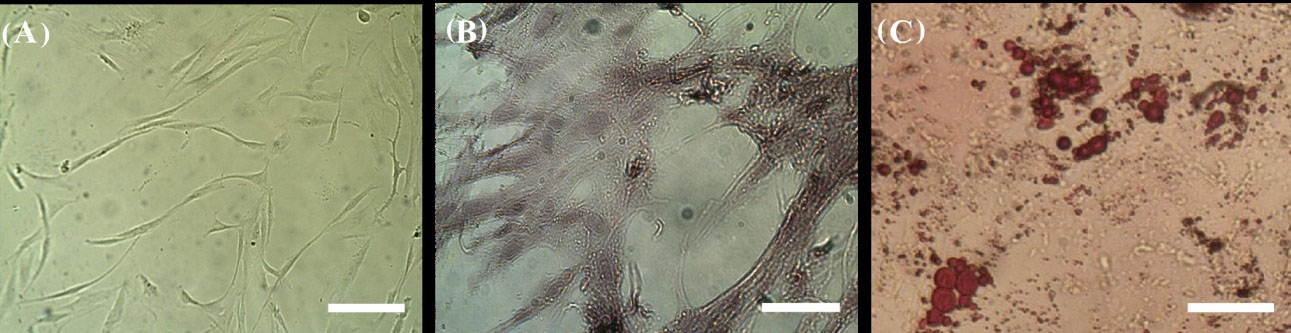

HEnSCs were plastic adherent, relatively elongated, spindle-shaped cells (Fig. 1 A). These cells were able to differentiate to osteoblasts and adipocytes (Fig. 1B and 1C). We used differentiation media for these purposes. According to these findings and flow cytometry results (data not shown), it can be stated that cell extraction was correct. HEnSCs had similar properties to MSCs.

Alizarin red and Oil Red O staining of differentiated hEnSCs. (A) Control, (B) osteogenic differentiation, and (C) adipogenic differentiation. HEnSCs were relatively elongated, spindle-shaped cells. These cells were able to differentiate to osteoblasts and adipocytes (scale bar is 100 µm).